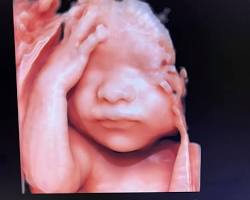

Siêu âm 5D là phương pháp siêu âm sử dụng sóng âm để tạo ra hình ảnh 3D của thai nhi, kết hợp với yếu tố thời gian (4D) và công nghệ xử lý hình ảnh tiên tiến để tạo ra hình ảnh chuyển động mượt mà, chân thực với màu sắc tự nhiên.

Nói cách khác, siêu âm 5D giống như bạn đang xem một video trực tiếp về em bé trong bụng mẹ, với độ phân giải cao và màu sắc sống động.

Hình ảnh siêu âm 5D thai nhi

- Hình ảnh rõ nét, chân thực: Giúp quan sát chi tiết khuôn mặt, cử chỉ, hành động của thai nhi.